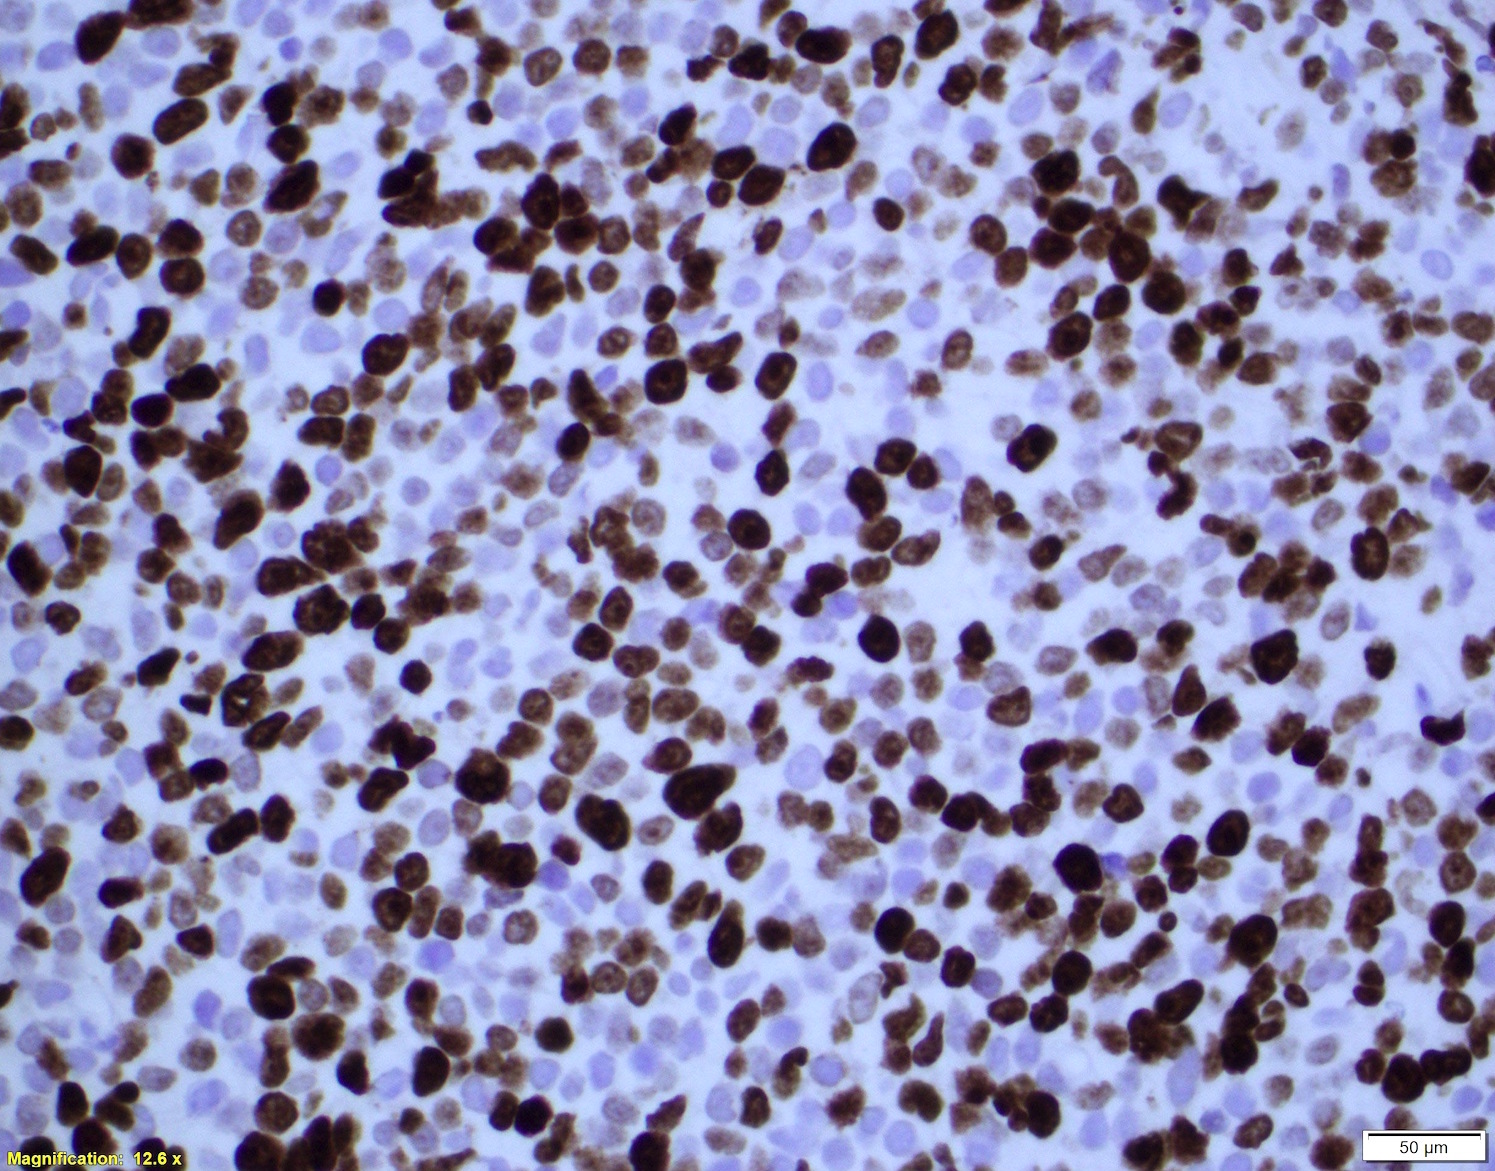

Microscopic (histologic) images

- Ki67 count (J Hematop 2009;2:103)

- Five independent high power fields count

- Avoidance of residual germinal centers, hot spots and proliferating T cells

- Note: Ki67 index is not sufficient to classify as blastoid or pleomorphic subtype

- Classical mantle cell lymphoma might also show high cell proliferation (Blood 2008;111:2385)